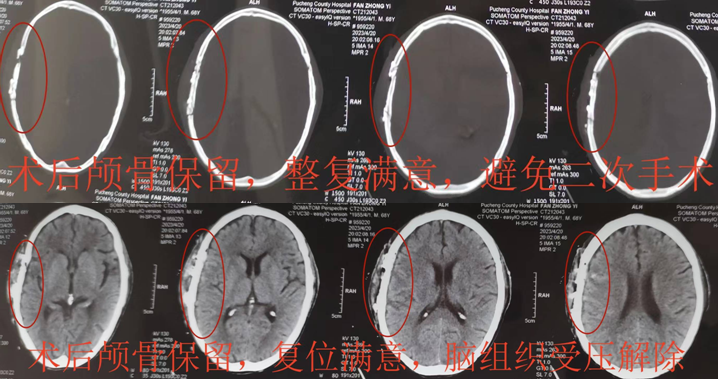

经过迅速有序的急诊术前准备后,患者被推入手术室,麻醉准备迅速完成,严格头皮裂伤清创后,利用现有的头皮裂伤口个体化设计手术入路,逐层切开头皮,严密止血,完整充分显露颅骨粉碎凹陷骨折,随着骨折片逐一摘取,实际的伤情远比头颅CT片上显示的严重而棘手,骨折的颅骨就像碎裂的玻璃板一样,骨头去除还是保留?去除简单快捷,风险小,也不违反手术原则;然而保留颅骨需要医生付出耐心,同时医疗的责任和压力全部需要术者承担!考虑到患者高龄,也许这次手术是唯一的机会,后续二次颅骨修补手术也许没有条件和机会实施。经过内心激烈的斗争,医者仁心的初心和“弘医弘道”的省医院训给了刘晓斌坚定的信念,经过近2小时认真仔细的操作,原本支离破碎的颅骨被完全整复,患者自体颅骨不仅得到保留,同时避免了二次颅骨修补手术的风险,也极大地节省了医疗费用。手术取得圆满成功,术后患者很快清醒,伤口愈合良好,神经功能恢复顺利,复查头颅CT显示颅骨整复塑型良好。